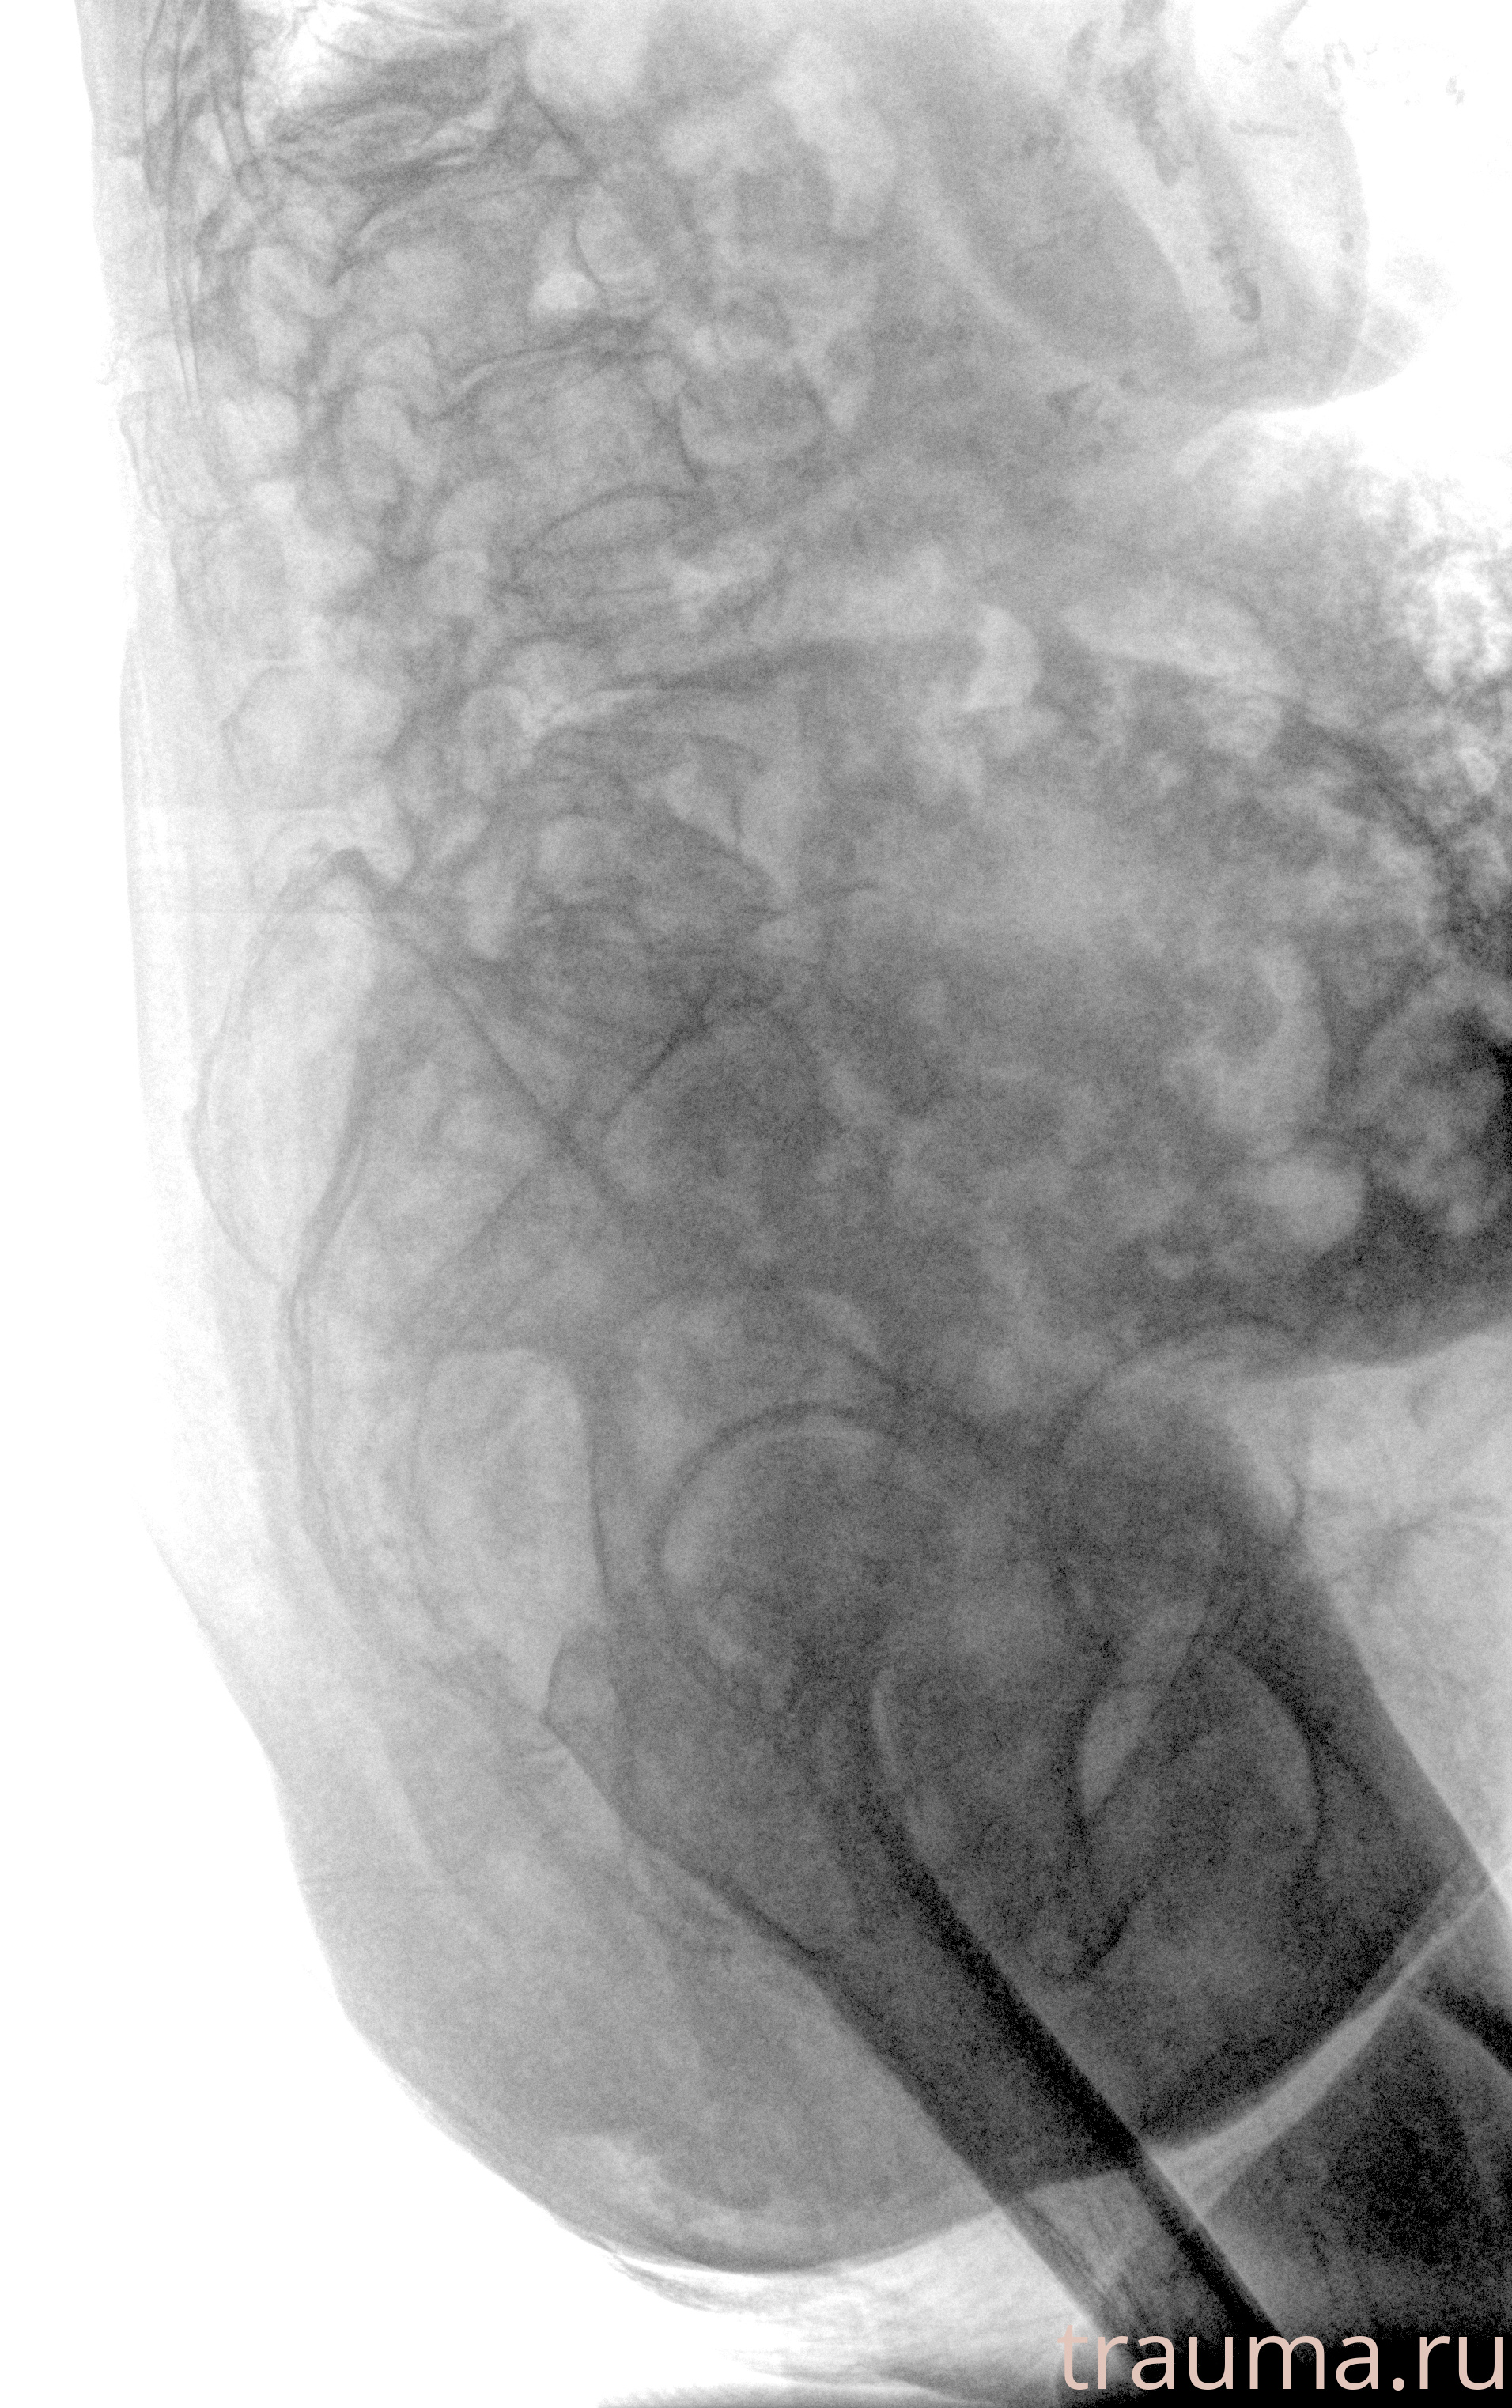

Рентгенограммы